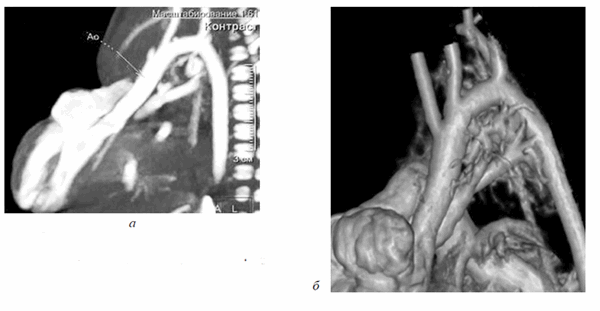

Ребенок был осмотрен коллегией специалистов: неонатологом, кардиологом, кардиохирургом, торакоабдоминальным хирургом, неврологом. Состояние ребенка расценено как стабильное, тяжелое, сознание на момент осмотра медикаментозно угнетено. При поступлении пациентке выполнена обзорная рентгенограмма грудной и брюшной полостей, визуализирующая сердечную тень в проекции эпигастрия, что дало представление о эвентрации сердца на переднюю брюшную стенку, однако не отражало анатомию внутрисердечных структур. Верхняя доля правого легкого ателектазирована, в дистальных отделах обоих легких выявлены признаки интерстициального отека легочной паренхимы. Контуры диафрагмы четкие, ровные (рис. 2). Учитывая отсутствие возможности проведения трансторакального ЭХО-КГ, в силу отсутствия кожно-апоневротического компонента, покрывающего сердце, в рамках предоперационного планирования принято решение о выполнении мультиспиральной компьютерной томографии (МСКТ) области грудной клетки с целью определения анатомии внутрисердечных структур и определения типа врожденного порока сердца.

Рис. 2. Обзорный ренгтеновский снимок, показывающий атипичную локализацию сердечной тени, асимметричное положение диафрагмы, неравномерную пневматизацию легочной ткани

Девочке 2-х суток жизни выполнена МСКТ в условиях медикаментозной седации с проведением проспективной ЭКГ-синхронизации, болюсного внутривенного контрастирования (в/в) препаратом Визипак 270 в объеме 6 мл в периферическую вену правой нижней конечности. Сканирование осуществлено на аппарате Philips Ingenity 128, kv 80, mas 350, протяженность сканирования 250 мм. Выполнено обзорное сканирование грудной клетки и брюшной полости до контрастного усиления, по результатам которого определяется диффузная неравномерность пневматизации легочной паренхимы, с наличием участков ателектазированной легочной ткани в верхних и нижних долях легких с обеих сторон, в обеих плевральных полостях определяется умеренное количество выпота (рис. 3). Сердце визуализировано вне грудной полости (рис. 4). В грыжевом мешке определяется фрагмент паренхиматозного органа брюшной полости, по нативным денситометрических показателям идентичный паренхиме печени (50HU), как показано на рисунке 5.

Рис. 3. Мультиспиральная компьютерная томография, мультипланарная реконструкция (MPR) легких в корональной проекции, в просвете трахеи интубационная трубка, пневматизация легких диффузно неравномерная с наличием участков ателектазированной легочной ткани

Рис. 4. Мультиспиральная компьютерная томография (МСКТ) легких, аксиальная проекция, патологический выпот в обеих плевральных полостях, эктопия сердца на переднюю грудную стенку

Рис. 5. МСКТ брюшной полости, аксиальная проекция, визуализирован грыжевой мешок, содержащий правую долю печени

После в/в контрастрования сканирование произведено в двух направлениях — каудокраниальном и краниокаудальном с целью визуализации анатомии сердца, определения сопутствующих пороков. В первую очередь требовалось уточнение анатомии камер сердца. По результатам исследования визуализированы полости правого и левого желудочков (ПЖ и ЛЖ), разделенные межжелудочковой перегородкой, с наличием дефекта в подклапанном отделе.

Правосторонняя предсердно-желудочковая конкордатность сохранена, анатомия правого предсердия определена наличием впадающего в него устья нижней полой вены. Левосторонняя внутрисердечная конкордантность оставалась под сомнением, так как ЛЖ сообщался с полостью, не имеющей в своей анатомии устьев легочных вен (рис. 6). Анатомия магистральных артерий также не являлась типичной. На (рис. 7, а) отчетливо визуализируется сформированный выходной тракт ЛЖ, корень аорты (Ао) с отходящими от лицевых синусов коронарными артериями, восходящий отдел Ао, дуга Ао с отходящими от нее брахиоцефальными сосудами, нисходящий отдел грудной Ао. Размеры всех вышеуказанных отделов магистральной артерии соответствовали росто-весовым показателям новорожденной (рис. 7, б).

Рис. 6. МСКТ, МPR. Четырехкамерная позиция, правосторонняя предсердно-желудочковая конкордантность сохранена, левосторонняя сомнительна

Рис. 7. МСКТ, сагиттальная проекция. (а) Визуализирован выходной тракт ЛЖ, сформированный корень Ао, восходящий отдел Ао, дуга Ао, нисходящий отдел Ао; МСКТ, объемная реконструкция (3D-volume rendering) сердца (б)

Источник кровоснабжения малого круга кровообращения в виде наличия легочной артерии (ЛА) отсутствовал, выходной отдел ПЖ не сформирован, правосторонняя предсердно-артериальная конкордантность нарушена. При детальной оценке полученных изображений визуализированы артериальные сосуды, отходящие от дуги Ао и направляющиеся к легким с обеих сторон. Общее количество больших аортолегочных коллатералей (БАЛК) — 2 (рис 8, а, б).

Рис. 8. МСКТ, MPR, определяются БАЛКи к правому и левому легким (а); МСКТ, 3D volume rendering, визуализация БАЛК к легким (б)

К правому легкому определено наличие двух ветвей БАЛК, одна из которых самостоятельно отходит от дуги Ао, вторая является ветвью БАЛКи, идущей также от дуги Ао, но имеющей деление на правую и левую ветви к одноименным легким соответственно. При анализе анатомии левого предсердия (ЛП) типичного расположения легочных вен (ЛВ) не отмечалось. Полость, сообщающаяся с ЛЖ, вбирала в себя единый венозный коллектор ЛВ, в который дренировались ЛВ обоих легких. Таким образом, был сделан вывод о том, что полость сообщающаяся с ЛЖ и включающая в себя единый венозный коллектор ЛВ, является ЛП (рис. 9). Анализируя структуры МПП и МЖП, отмечались множественные дефекты перегородок.

Рис. 9. МСКТ, аксиальная проекция, показан единый коллектор легочных вен

По результатам проведенного исследования было сделано заключение о наличии у пациента врожденного порока сердца — атрезия ЛА IV типа, БАЛКи ДМПП, ДМЖП, единый коллектор ЛВ в условиях эктопии сердца.